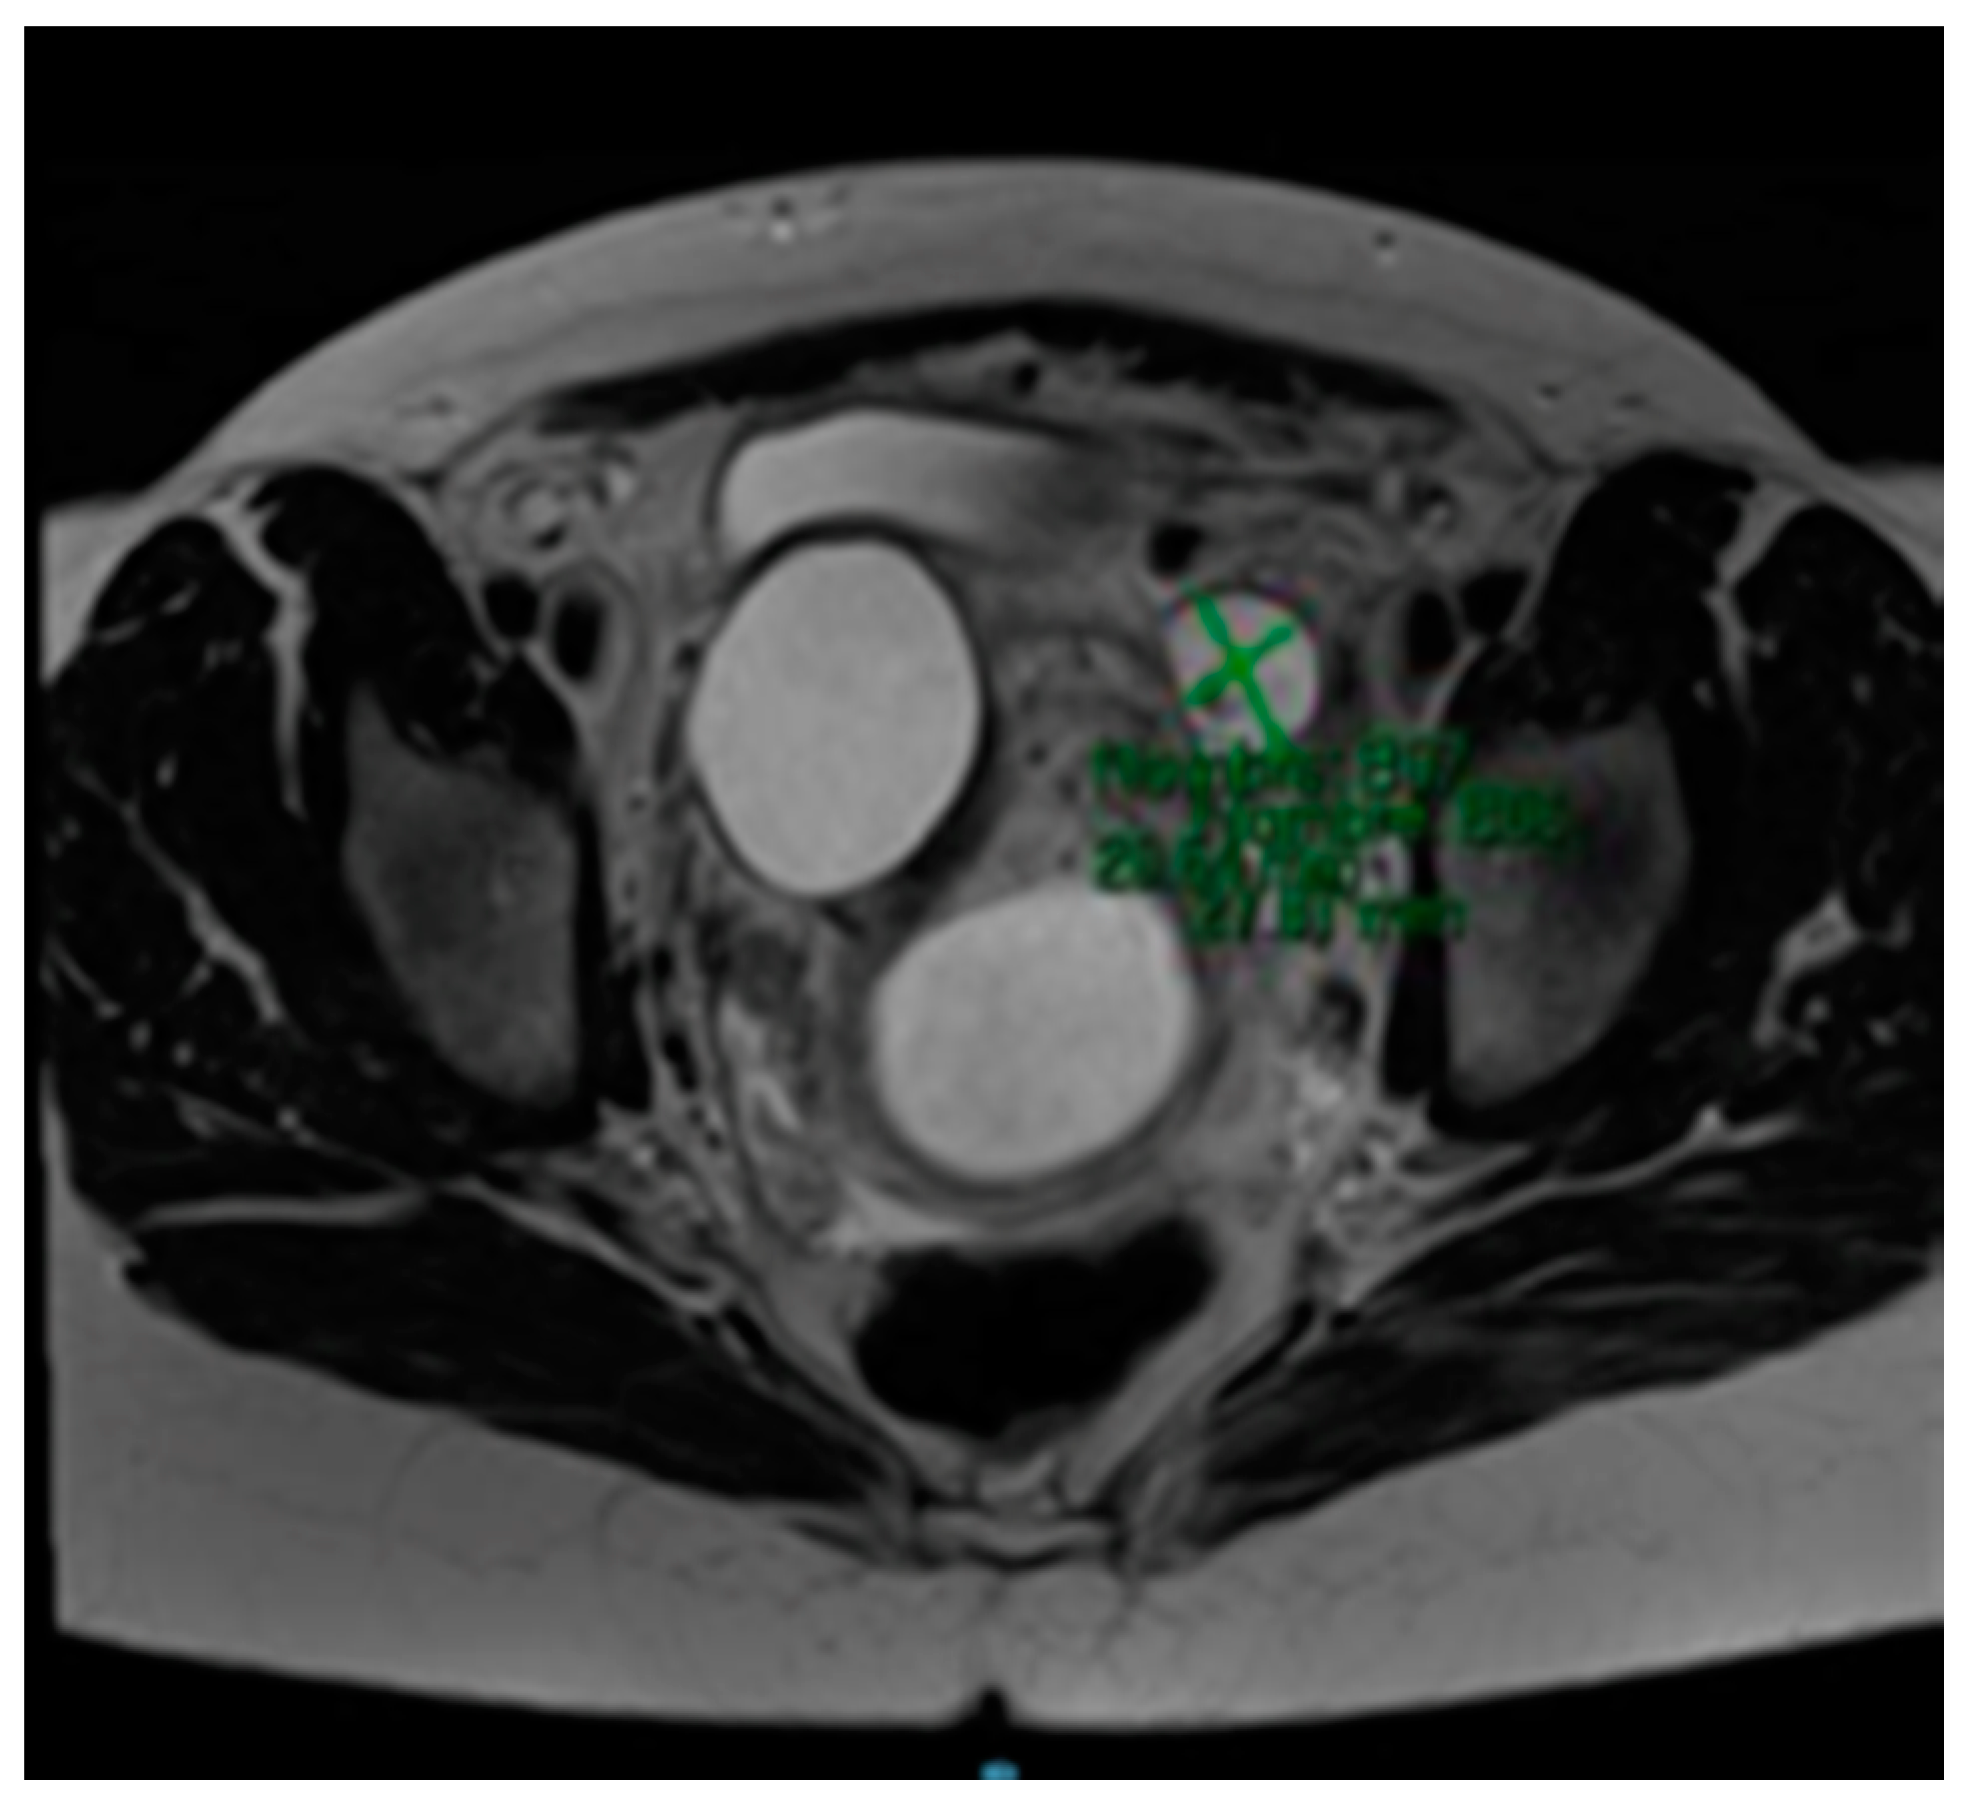

The MRI (Magnetic Resonance Imaging) scan showed 53 mm × 46 mm thin-walled cysts with a septum in the right paracervical area, another 27 mm × 20 mm cystic formation in the left hemipelvis (Figure 2 and Figure 3) and presacral 2 cm cysts containing a solid pole.

Figure 3. MRI scan compatible with 53 mm × 46 mm cystic formation in the right paracervical area.